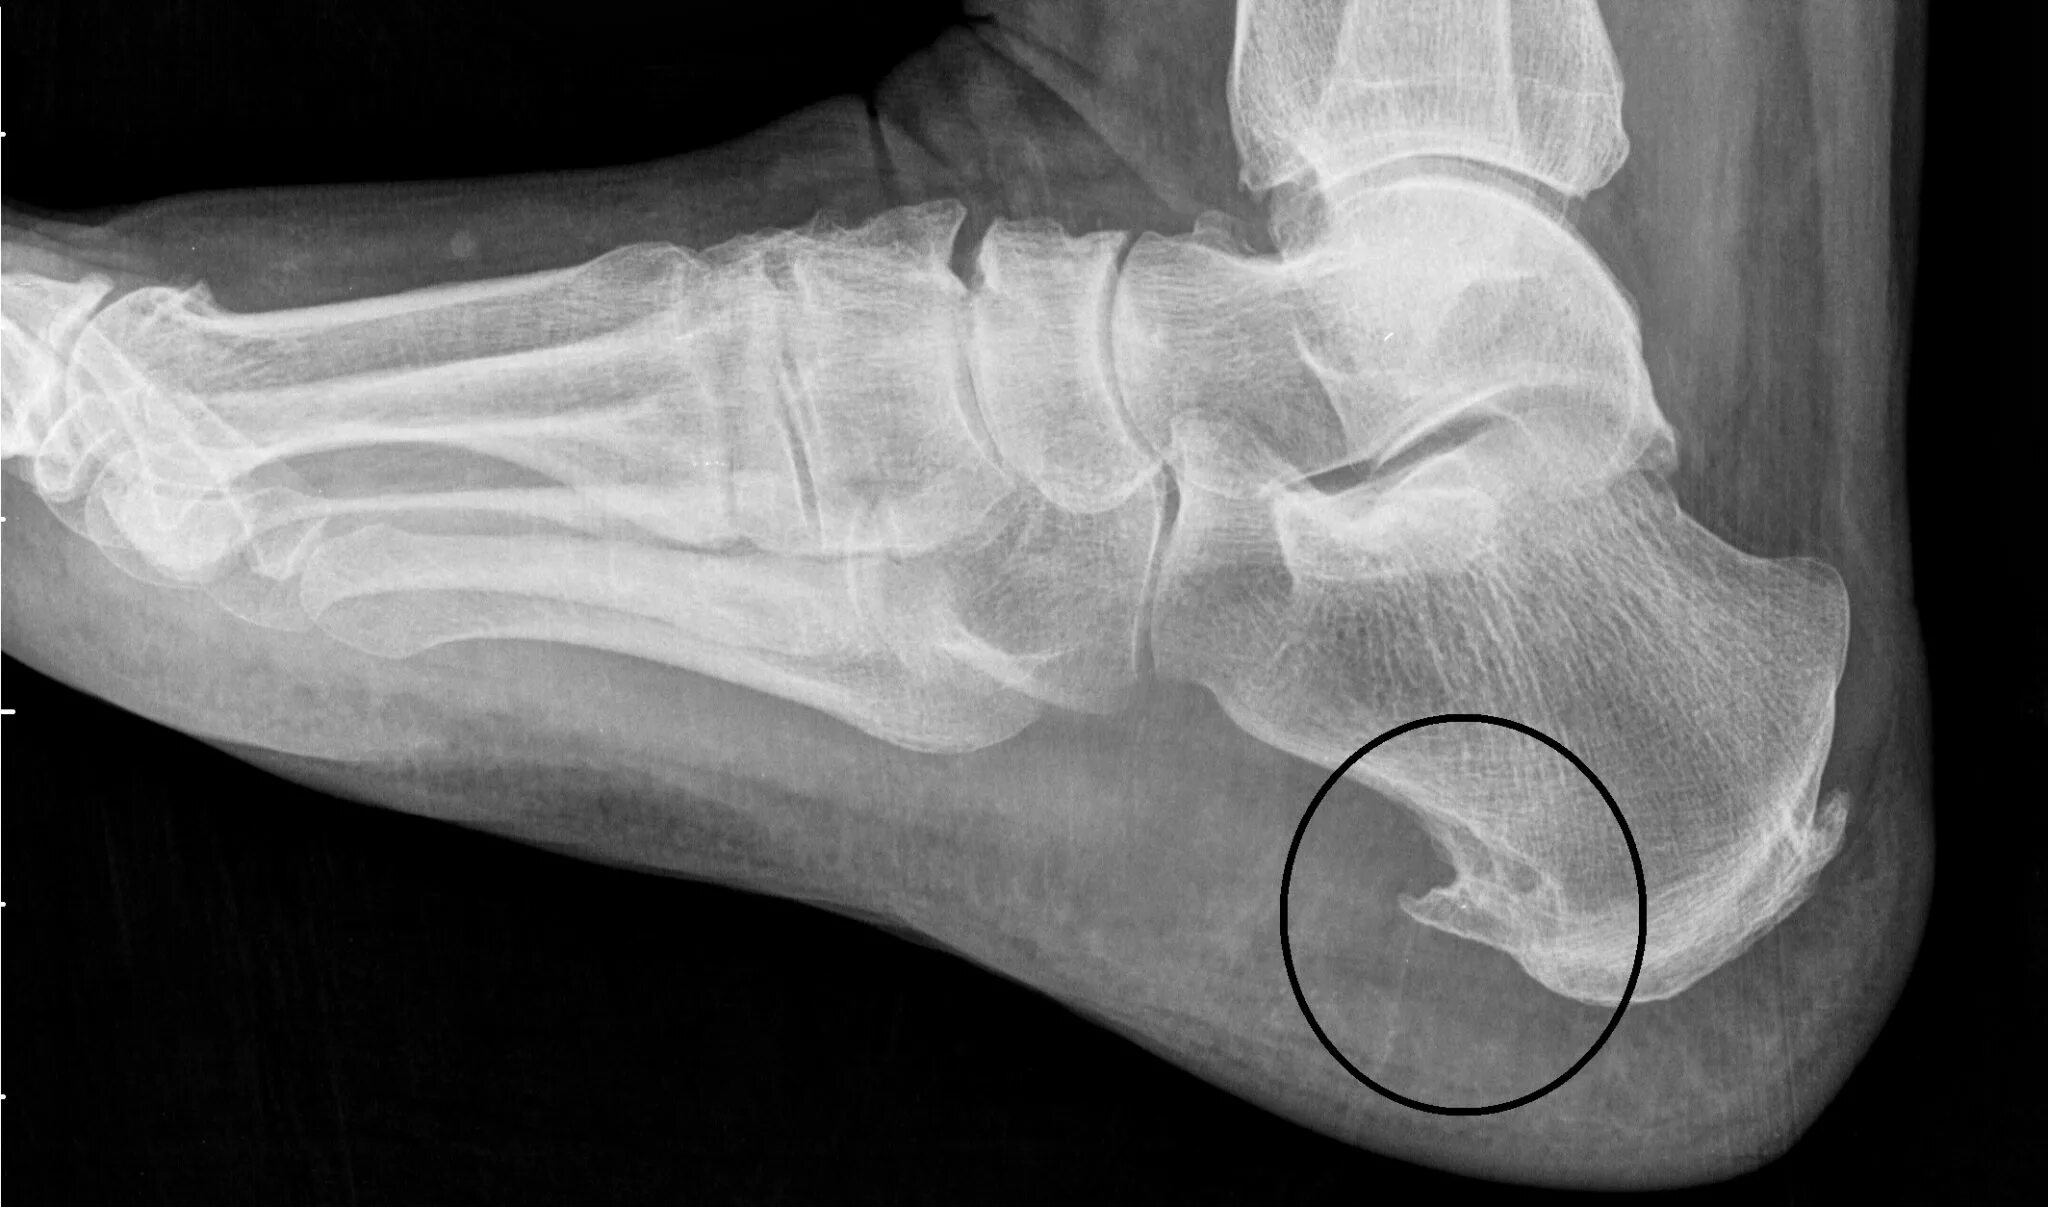

Как называется пяточная шпора